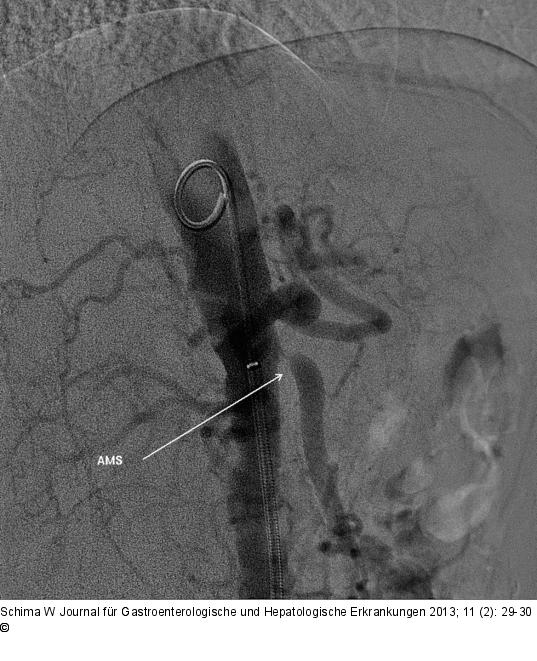

Abbildung 2a: Abgangsstenose Die Angiographie zeigt eine hochgradige Abgangsstenose der A. mes. sup. |

Die Angiographie zeigt eine hochgradige Abgangsstenose der A. mes. sup. |